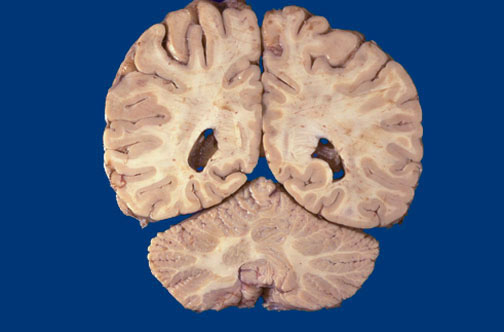

Identify the following regions of the normal brain by clicking in the image below:

Occipital Lobe - Cerebellum